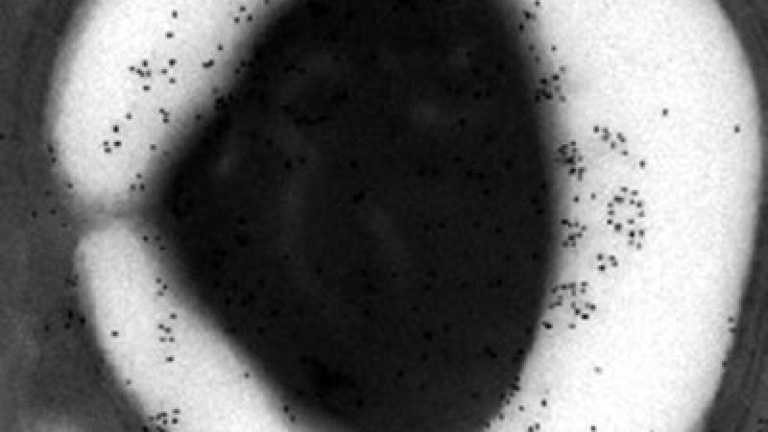

Un grupo de investigadores franceses ha dado un pequeño paso hacia la creación de una patata transgénica que funcione como vacuna contra la malaria, una enfermedad que mata a casi un millón de personas cada año. Los científicos, del Centro de Infección y de Inmunidad de Lille, han alimentado con almidón genéticamente modificado a ratones y han observado "una protección significativa" contra el parásito que causa la malaria. El almidón, una cadena de azúcares, es la principal reserva de energía en el maíz y la patata.

Estable y barataLos investigadores, que publican sus resultados esta semana en la revista online PLoS ONE, han modificado genéticamente el almidón extraído de un alga para que vehicule proteínas capaces de generar en el organismo una reacción de defensa contra el parásito. La eficacia de estas proteínas ya había sido demostrada en ensayos con otras vacunas.